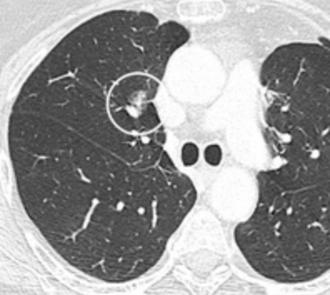

CT — Lung Nodule with Vascular Convergence

CT showing lung nodule with converging pulmonary vessels, a sign suggesting malignancy

CT Downloaded 2026-03-15

Ct

Lung Window 120 kVp W:1500 L:-600

Wikimedia Commons: CT of lung nodule with vascular convergence.png